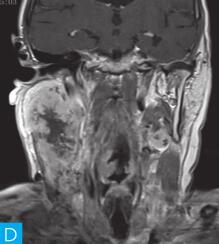

(1)扁桃体鳞癌并颈部转移性淋巴结:扁桃体可发生多种原发性恶性肿瘤,鳞状细胞癌发生率较高,恶性淋巴瘤次之。扁桃体鳞癌多呈浸润性生长,病变形态多不规则,边界常不清楚,且可融合而呈分叶状,肿瘤内易囊变、坏死,常导致密度及信号不均匀,增强后大多数为明显不均匀强化,呈环形强化,环壁厚,不规则。鳞癌常有深部侵犯,侵犯范围广,且易侵犯咽旁间隙。扁桃体癌分化程度较差,侵袭性强,早期即有淋巴结转移。其颈部淋巴结转移很容易发生中心坏死,淋巴结直径可达3~4cm,其典型的影像学表现为不规则环形强化伴中心坏死区(图2)。

图2 扁桃体鳞癌并颈部转移性淋巴结:A.咽喉部MR横断面平扫T1WI;B.咽喉部MR横断面T2WI;C.咽喉部MR横断面增强T1WI;D.咽喉部MR冠状面增强T1WI